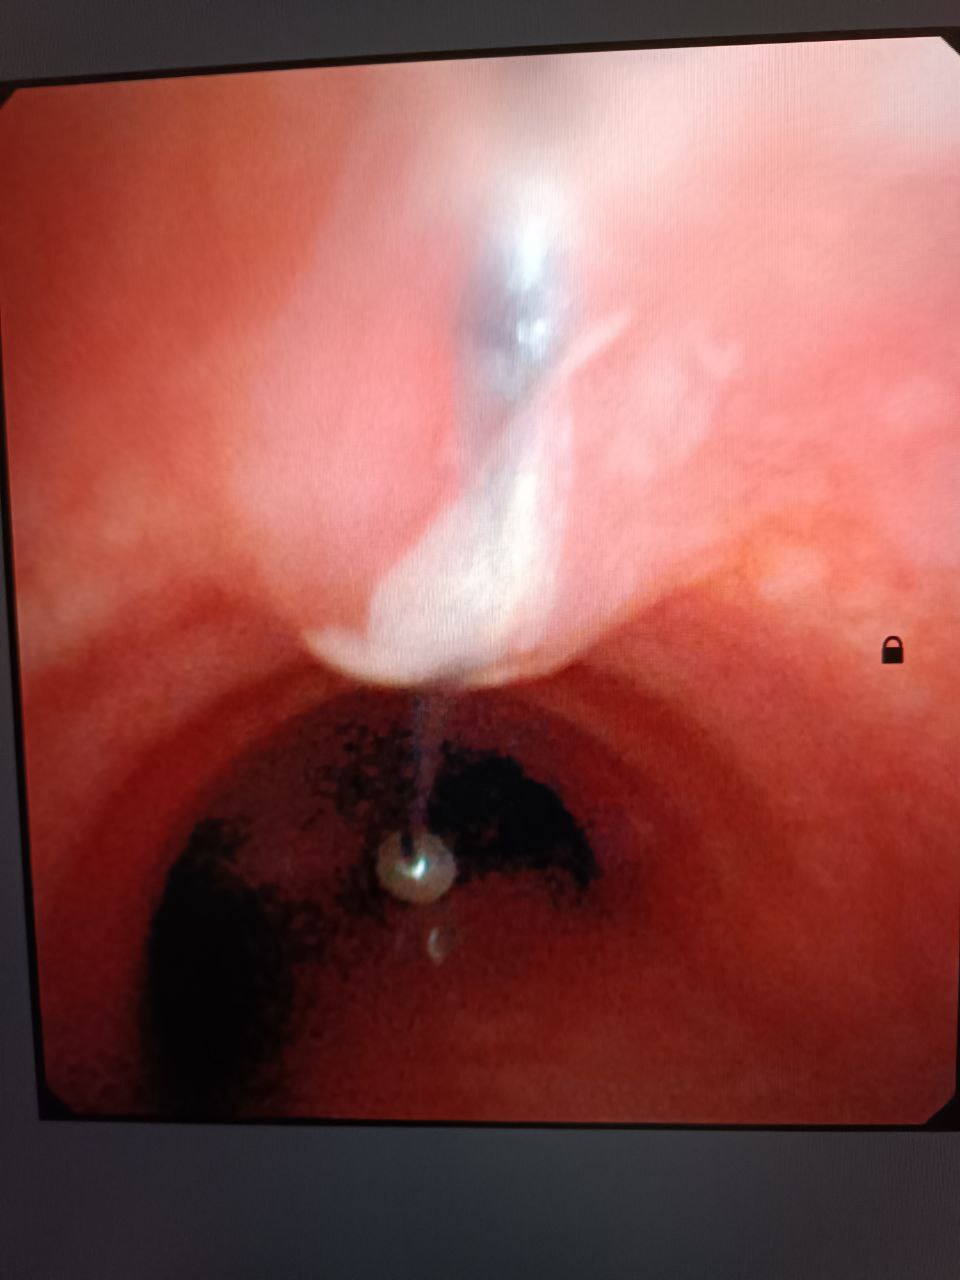

Завдяки високій кваліфікації чергового хірурга та анестезіологічної бригади, ендоскопічним методом було видалено стороннє тіло - голка довжиною 4 см.

Підлітку під наркозом провели бронхоскопію та дістали шпильку, яка гострим кінцем встромилася у слизову та нікуди не рухалася.

"Ця ювелірна робота була проведена в міській лікарні завдяки сучасному ендоскопічному обладнанню, яке використовується в міській лікарні, раніше ж такі випадки лікувались в обласному центрі", - йдеться у повідомленні.